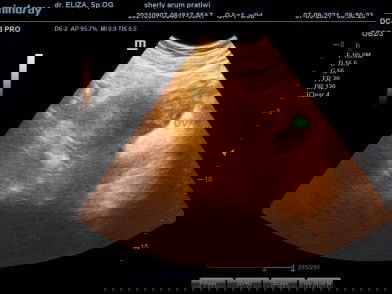

Assalamualaikum bunda, Aku mau sharing siapa tau nih ada yg samaan kaya aku, Aku terakhir mens 11 mei 2021, Bulan juni,juli,agustus aku tespek hasilnya negativ,, Lalu bulan september awal aku tespek alhamdulillah positif tapi ditanggal 3,4,5 masih samar blm terlalu jelas Lalu ditanggal 7 aku usg untuk melihat lebih jelasnya, karna dokter masih ragu sebab ada kaya gumpalan darah kata dokter masih blm tau ini darah yg numpuk karena aku udah 3 bulan gak mens, apa emng bakalan jadi calon janin, Lalu dokter memberitahu aku untuk tespek ulang, alhamdulillah tetep garis 2, dan tambah jelas ya meskipun blm sejelas yg atas nya tapi seengaknya ngebuat aku positif thingking , lalu bidan bilang perkiraan masih 1 bulan Aku dikash obat namanya microgest selain untuk memperkuat kandungan ia juga untuk membantu pertumbuhan janin, Doakan ya bunda semoga kehamilan aku baik baik saja sampai persalinan nanti dan sehat 2" nya.. Penantian 3 tahun 😥 #bantusharing #firstbaby